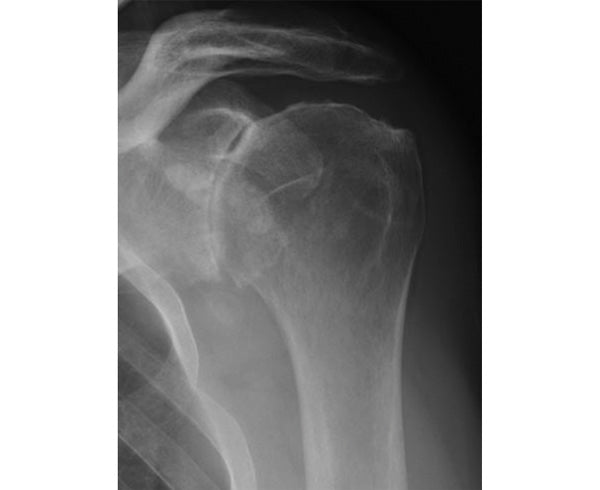

Symptoms of GH joint arthritis include shoulder pain, stiffness, end range of motion pain (pain that worsens towards the end of your shoulder range), and pain at night. The pain is often described as a “deep ache” and becomes progressively worse over time. You may hear and feel a grinding sensation as you move your shoulder.

Your healthcare provider will evaluate your range of motion, measure strength, and perform special tests to help diagnose the source of your shoulder symptoms. They will use the results of their exam to determine if you need further testing (e.g. x-ray, MRI, CT scan).